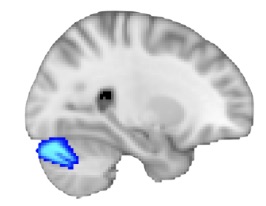

Next, we tested whether activation changed as a function of IQ while controlling for age and sex. The map below shows the Words contrast in the AVH− group in the Right cerebellar Crus I, which was the only group and condition where a positive association with IQ survived correction.

Right cerebellar Crus I region

Figure 4. Whole-brain activation maps showing the effect of IQ during the words contrast in the AVH− group. Highlighted regions indicate voxels where activation increases with IQ (Z > 2.3, cluster-corrected p < 0.05).

In addition to the auditory cortex, we examined the right cerebellar Crus I, a region in the posterior cerebellum that has been linked to higher-level cognitive and language-related processes. Prior research suggests that this region may play an important role in syntactic and cognitive aspects of speech processing, making it a relevant target for understanding variability in schizophrenia [3].

Unlike the auditory cortex, the right cerebellar Crus I showed different patterns of association with IQ across participant groups. In the healthy control group, IQ was positively associated with activation across all three speech conditions. Among participants with schizophrenia who experienced auditory verbal hallucinations (AVH+), the relationship between IQ and activation was negative across all contrasts. In contrast, participants with schizophrenia who did not experience hallucinations (AVH−) showed positive associations across all contrasts.

Figure 3. Right cerebellar Crus I region of interest.

The clearest finding emerged in the Words condition, where the relationship between IQ and right cerebellar Crus I activation was statistically significant in both schizophrenia groups. For the AVH+ group, higher IQ was associated with lower activation in right Crus I, which alligns with previous researches that talks about this idea as well [4, 5]. Meanwhile, for the AVH− group, higher IQ was associated with higher activation. This suggests that cognitive ability may relate to speech processing differently depending on hallucination status.

Overall, these findings suggest that the right cerebellar Crus I may capture important cognitive differences in how speech is processed in schizophrenia. Rather than reflecting basic auditory perception alone, this region may be more sensitive to the higher-level language and cognitive processes that vary across individuals.